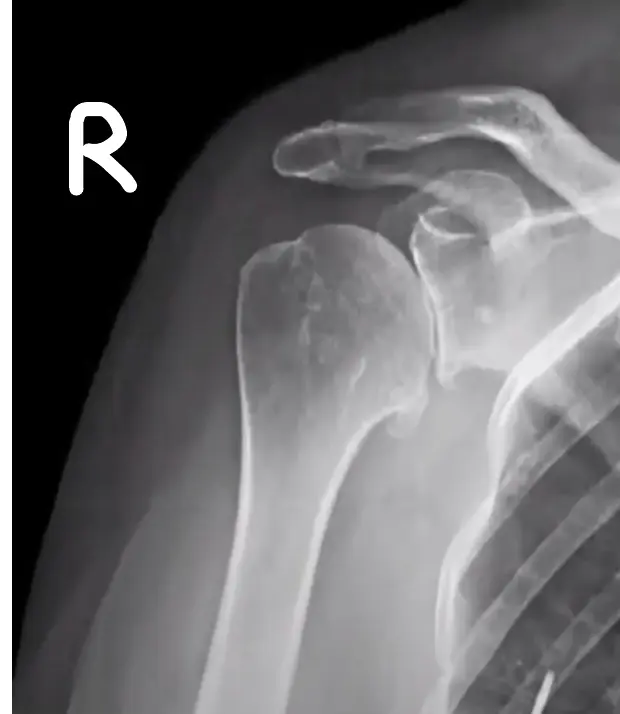

Section 3: Shoulder Pathology & Examination

Questions 17-20: Shoulder Injuries and Tests

Clinical Scenario: 45 years old male fell from height and landed on his shoulder and presented to your clinic with painful shoulder.

Q17: What is the following test name and what does it test?

Apprehension test for anterior shoulder instability

Q18: What is the following test name and what does it test?

Empty can test for Supraspinatus power